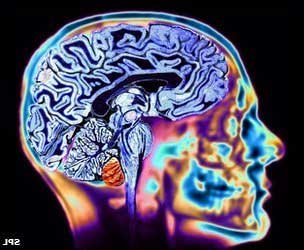

- Аневризма сосудов головного мозга. Этот тип аневризмы встречается наиболее часто. При данной патологии происходит увеличение артерий головного мозга. Заболевание зачастую протекает без выраженных симптомов, и пациенты могут жаловаться лишь на головные боли. Без своевременной диагностики это состояние может привести к серьезным осложнениям, вплоть до летального исхода. Чаще всего поражается левая внутренняя сонная артерия.

- Компьютерная томография (КТ) или магнитно-резонансная томография (МРТ) головного мозга.

- Ангиография сосудов головного мозга.